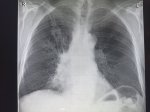

IMG20251016095819.jpg

Здравствуй двачик! Тут все мои друзья, потому бущем вместе с вами играть в доктора. Я буду постить фоточки а вы угадывать пиздецомы.

Аноним 16/10/25 Чтв 09:17:43 #25 №325600106

>>325599918

>>325598580 (OP)

А вот это округлое ниже левой ключицы что? Справа похоже на долевую пневмонию правостороннюю